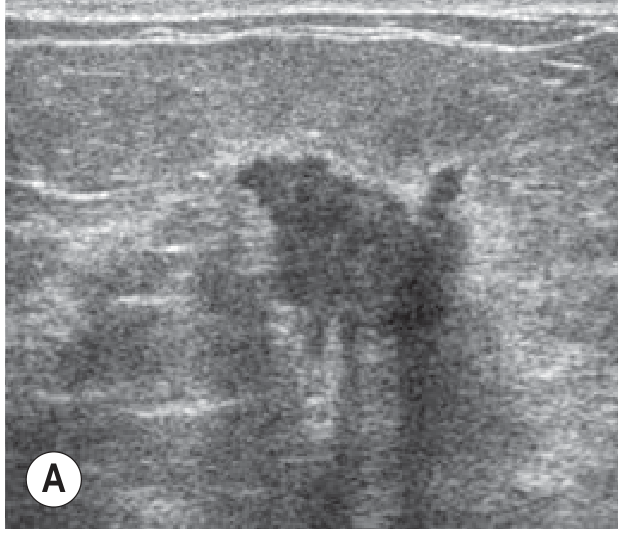

Ultrasound of invasive breast carcinoma — irregular hypoechoic mass with acoustic shadowing and echogenic halo

Ultrasound of invasive carcinoma: irregular hypoechoic mass with acoustic shadowing and echogenic halo — typical of malignancy. — Grainger & Allison's Diagnostic Radiology